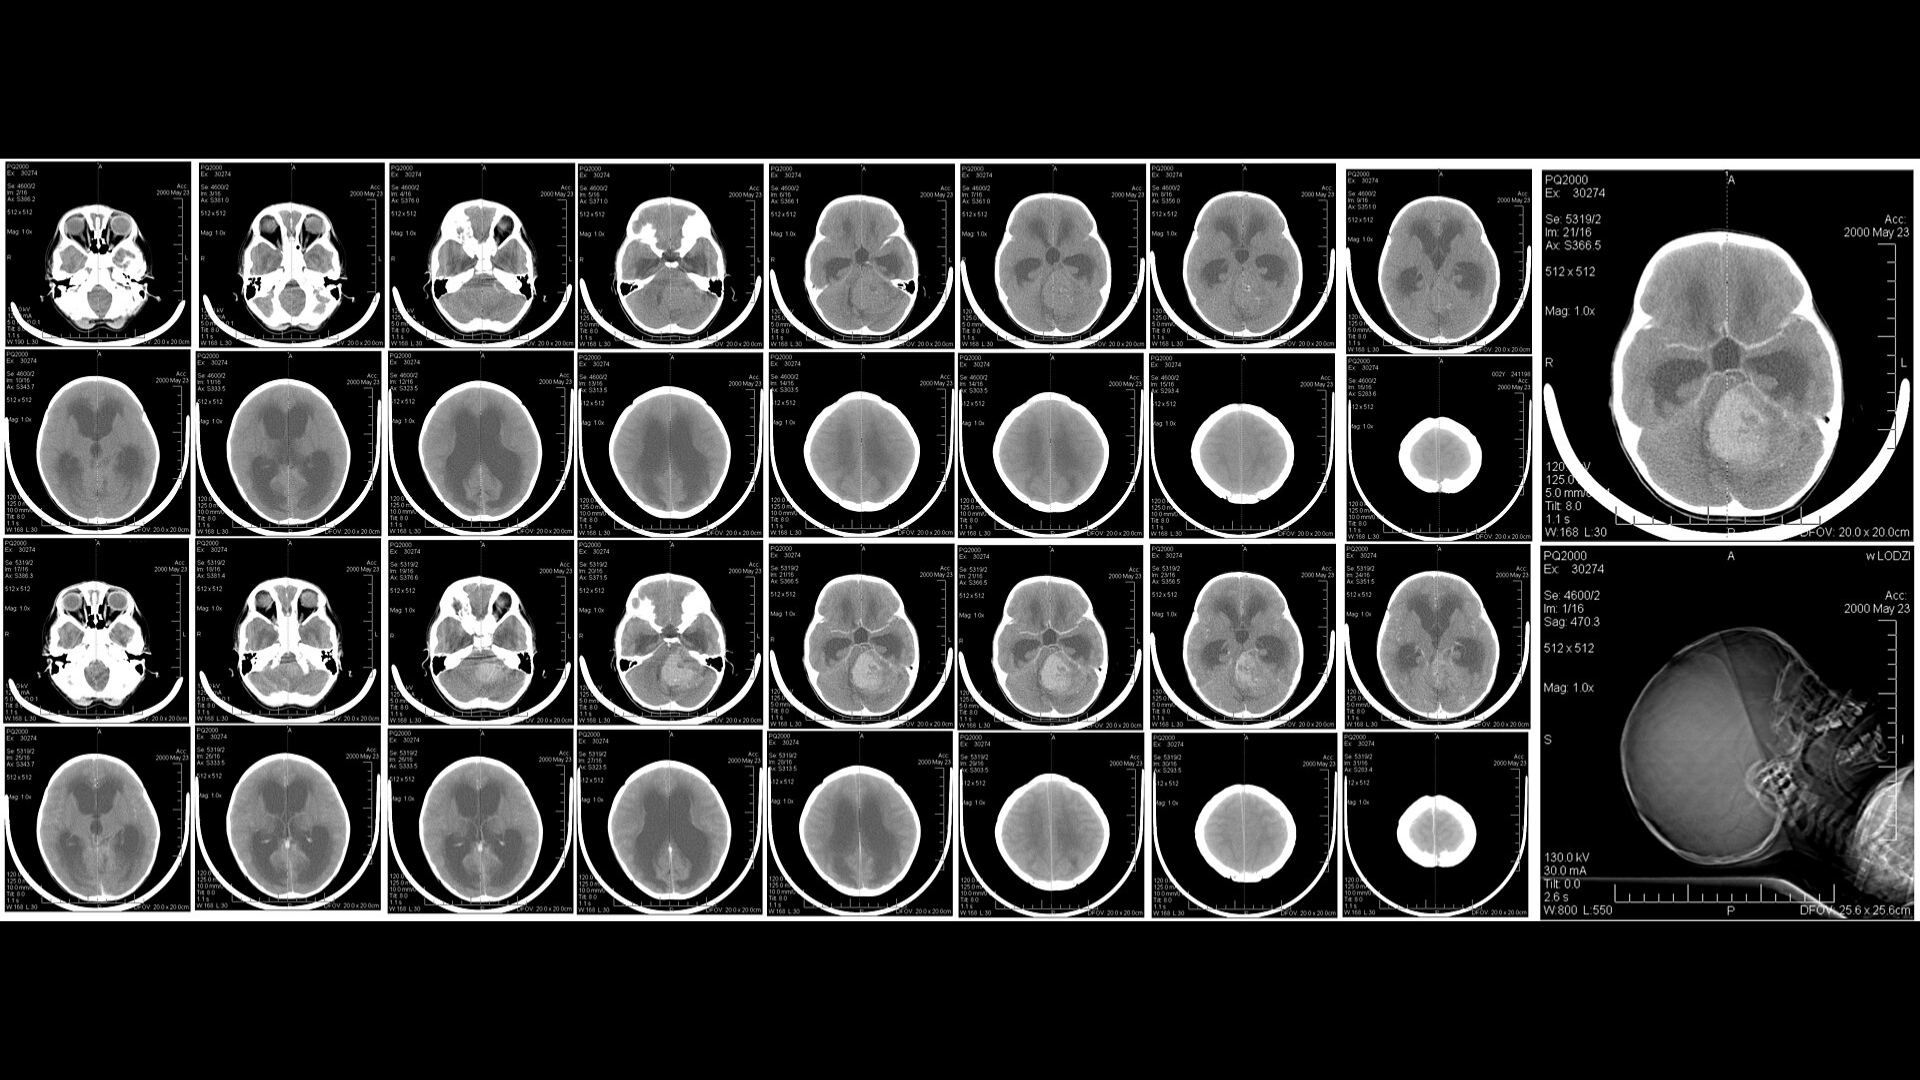

• 進階診斷:最先進的影像(例如 PET-CT、Siemens MRI)和分子剖析,以找出腫瘤的代謝漏洞。

• 醫療記錄:最近的診斷報告、影像掃描(如 CT、MRI、PET-CT)、病理結果和治療史。接受數位或實體複本。